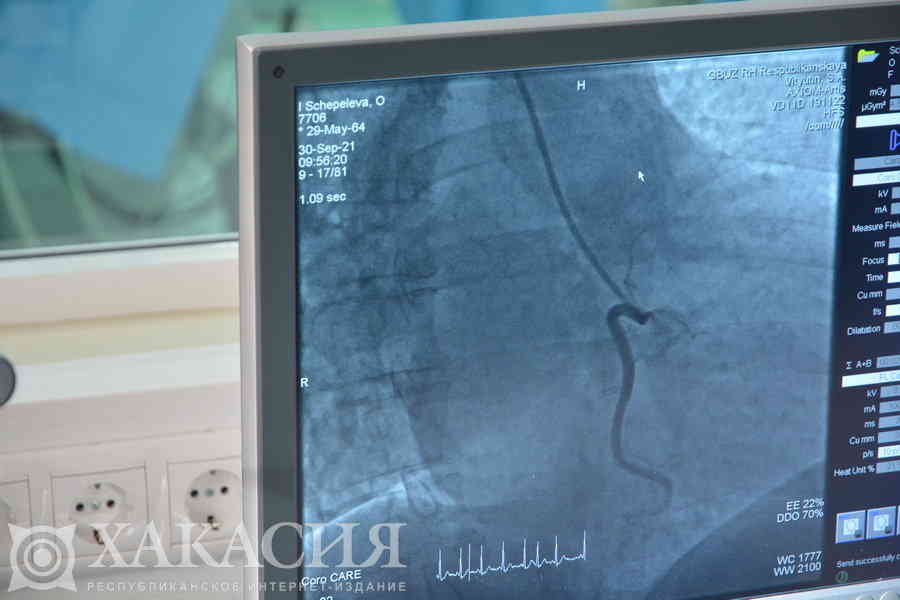

В республиканской клинической больнице имени Г. Я. Ремишевской запущена в работу новая ангиографическая установка, с помощью которой проводятся исследования и операции у пациентов с сосудистыми заболеваниями. Современное медицинское оборудование стоимостью около 56 миллионов рублей поступило в Хакасию в рамках федерального проекта «Борьба с сердечно-сосудистыми заболеваниями».

Главная функция усовершенствованного аппарата — визуализация. Чудо-машина, как её уже окрестили врачи, позволяет получить подробное изображение кровеносных сосудов и оценить характер кровотока. Ангиограф помогает доктору более точно и быстрее установить диагноз и провести манипуляции. Кроме того, это сокращает время операции с трех часов до 30-40 минут, при этом хирургическое вмешательство проводится без общего наркоза, а под местной анестезией. После этого пациенты быстрее восстанавливаются и могут выписаться из больницы уже на третьи сутки. Оборудование незаменимо при лечении ишемической болезни сердца, атеросклерозе, нарушениях мозгового кровообращения и других заболеваниях сосудистой системы. Также его применяют и для диагностики онкологических заболеваний.